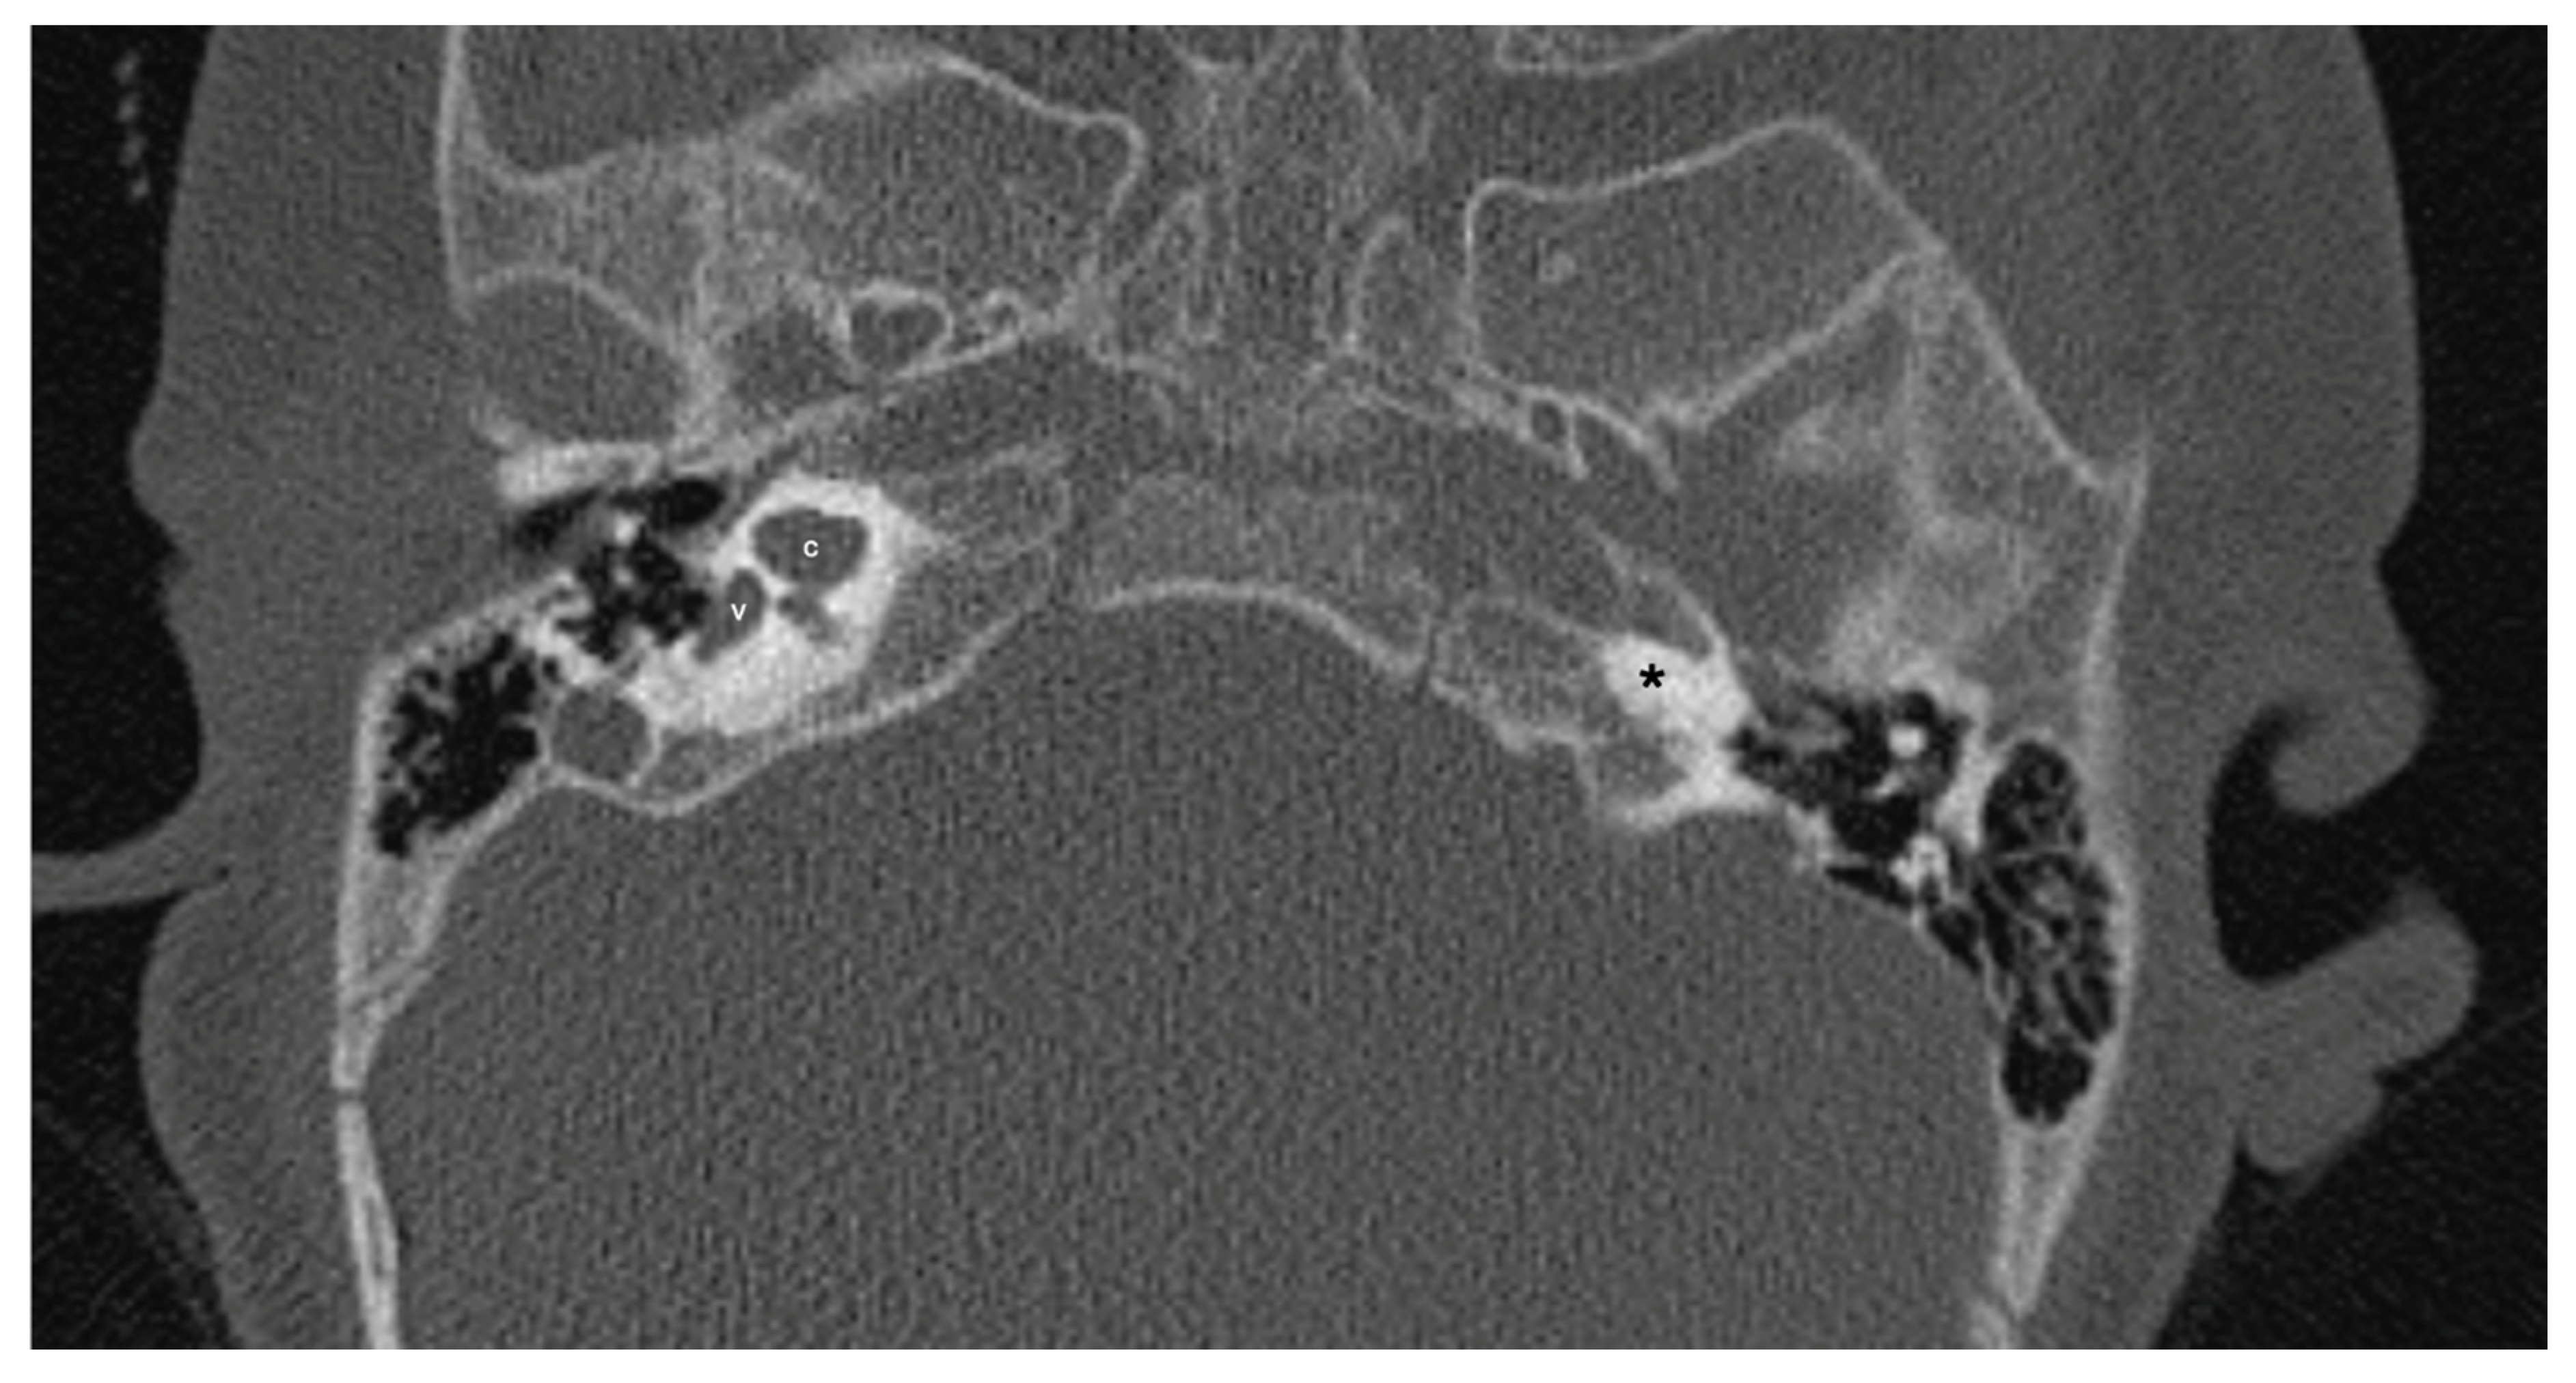

One patient exhibited IP-1 in the right ear and LA in the left ear. The right vestibule was hypoplastic, and the SCCs appeared as a single bud. The diameters of the right IAC and cochlear nerve were within normal limits. However, the stapes, oval and round windows, cochlea, vestibule, SCCs, IAC, and vestibulocochlear nerve could not be detected in the left ear. Cochlear implantation was performed in the right ear of this patient (Figure 3). Bilateral IP-3 anomalies were detected in 2 siblings. In these cases, the oval and round windows were also malformed. While both cochlear nerves of one sibling exhibited hypoplasia, the cochlear nerves of the other sibling were within normal limits as they were thicker than the facial nerves (Figure 4).

Figure 3. Patient with right-sided IP-1 (incomplete partition type-1) and left-sided LA (labyrinthine aplasia). On the right side the cochlea (c) and the vestibule (v) are clearly differentiated. The cochlea has a near normal size but lacks the entire modiolus and interscalar septa. None of the labyrinthine structures except the dense otic bone (*) can be seen on the left side.